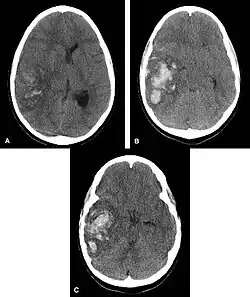

Multiple intraparenchymal hemorrhage

Intraparenchymal hemorrhage is one form of intracerebral bleeding in which there is bleeding within brain parenchyma. The other form is intraventricular hemorrhage).[1]

Intraparenchymal hemorrhage accounts for approximately 8-13% of all strokes and results from a wide spectrum of disorders. It is more likely to result in death or major disability than ischemic stroke or subarachnoid hemorrhage, and therefore constitutes an immediate medical emergency. Intracerebral hemorrhages and accompanying edema may disrupt or compress adjacent brain tissue, leading to neurological dysfunction. Substantial displacement of brain parenchyma may cause elevation of intracranial pressure (ICP) and potentially fatal herniation syndromes.